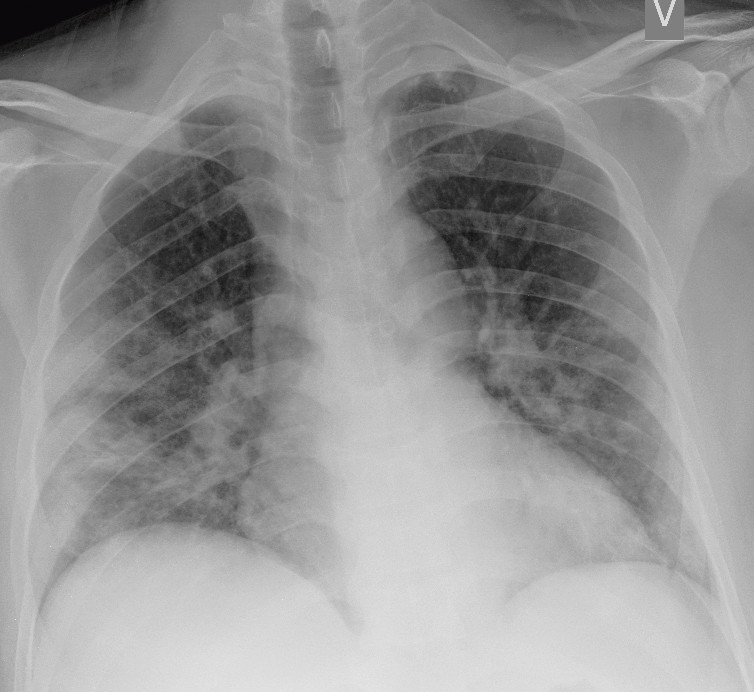

I et materiale fra Hongkong hadde 69 % funn på røntgen thorax før behandling (baseline), men 9 % hadde funn på røntgen thorax før positiv PCR (14). Sensitiviteten for røntgen thorax var 69 % og for PCR 91 %. Vanligste røntgenfunn var bilateral konsolidering og mattglassfortetninger med perifer og kaudal distribusjon. Forandringene var mest uttalt 10–12 dager etter symptomdebut. Figur 1 og figur 2 viser typiske funn på røntgen thorax ved covid-19.

Hos inneliggende pasienter kan et sengebilde i tidlig stadium være nyttig som sammenligningsgrunnlag for tolking av bilder tatt senere. Hos pasienter med alvorlig sykdom vil det være indisert med sengebilder for kontroll av medisinskteknisk utstyr (figur 3), men det er ikke indisert med daglig, rutinemessig røntgen thorax hos stabile pasienter. I forløpet av sykdommen vil det være indisert med sengebilde ved mistanke om komplikasjoner og ved oppfølging og monitorering av sykdomsprogresjon.